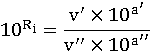

- доза, вызывающая гибель 50% животных

- доза, вызывающая гибель 50% животных